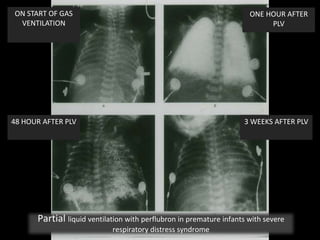

ON START OF GAS

VENTILATION

ONE HOUR AFTER

PLV

48 HOUR AFTER PLV 3 WEEKS AFTER PLV

Partial liquid ventilation with perflubron in premature infants with severe

respiratory distress syndrome